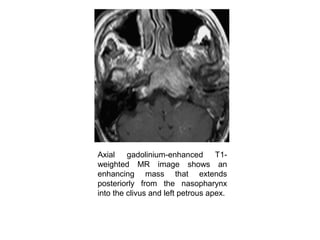

Axial gadolinium-enhanced T1-

weighted MR image shows an

enhancing mass that extends

posteriorly from the nasopharynx

into the clivus and left petrous apex.